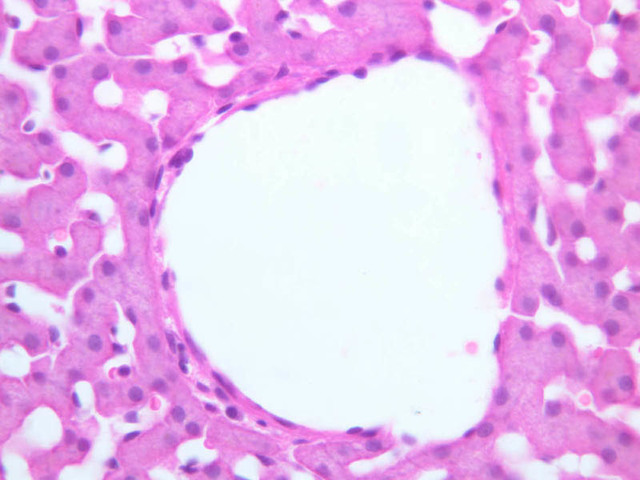

Examine the H&E-stained sections of liver (slides B-29 [10x, 20x, 40x-labeled] [2.5x-labeled, 10x, 20x, 40x] [10x-labeled, 20x, 40x-labeled] and B-30 [2.5x, 10x-labeled, 20x]). At low power, identify the connective tissue capsule (Glisson’s capsule), central veins and portal triads (portal canals). Note that the cells of the liver parenchyma (hepatocytes) appear as cords--more accurately, plates--of cells that radiate out from the central veins and partially enclose blood spaces known as hepatic sinusoids. Note that the plates of hepatocytes appear to branch and fuse and that, as a rule, they are only one or two cells thick. Do you see any binucleate hepatocytes?

Using the 10X (B-29, B-30)and 40X (B-29) objectives, examine several portal triads, noting the variable number of profiles of hepatic artery, portal vein and bile duct that comprise the portal triad. Near the boundary between adjacent lobules, try to find some of the small elements of the bile duct system known as canals of Hering.

(1) Identify the portal triads that define the boundaries of a “classic” liver lobule (B-29). Since it surrounds a central vein, the classic lobule may be thought of as emphasizing the endocrine functions of the liver.

(2) Move the slide so that a portal triad is at the center of the microscopic field, then identify the three central veins that define the boundaries of the portal lobule that surrounds the reference portal triad. Since an interlobular bile duct is at the center of a portal lobule, the portal lobular interpretation emphasizes the exocrine functions of the liver (B-31).

(3) A liver acinus is roughly elliptical in section. Its shorter axis (equator) is defined by the terminal branches of the hepatic artery and portal vein, which course along the boundary between adjacent classic lobules; its longer axis is defined by the two central veins nearest the equator (B-29). Although it is more difficult to visualize a liver acinus than a classic or portal lobule, the concept of acinar organization is very useful because certain features of liver metabolism best fit the acinar model.